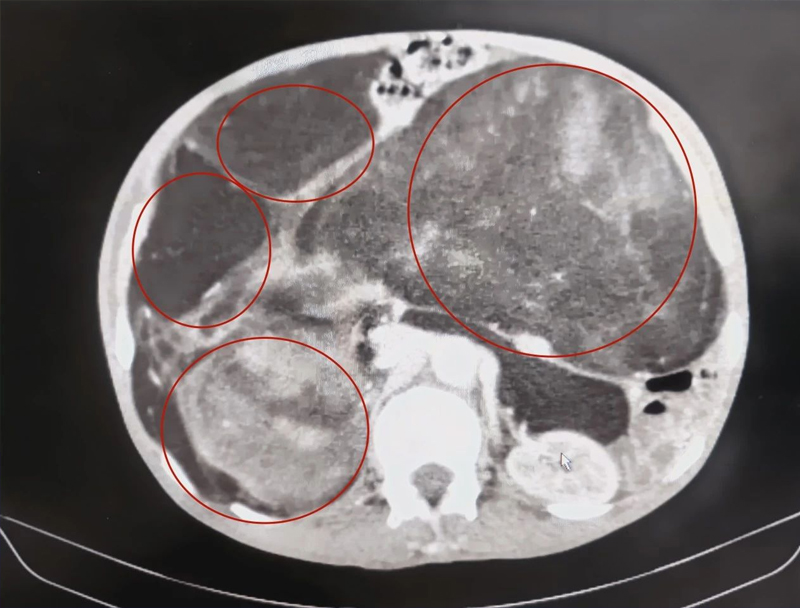

经过进一步检查,吴大爷的肿瘤几乎已经占满整个腹腔,上至肝脏,下达盆腔。而且紧贴着右侧肾脏、右侧肾上腺、右侧输尿管和腹腔大血管,犹如天然的“雷场”,手术不仅要拆除这个“巨型炸弹”,而且不能损伤周围大血管,难度及复杂性可想而知。但面对患者无比强烈的治疗意愿和家属的信任,并且王凯民主任有过多次切除腹部巨大肿瘤的手术经验,他还是接下了这挑战!

术前检查肿瘤几乎占据整个腹腔